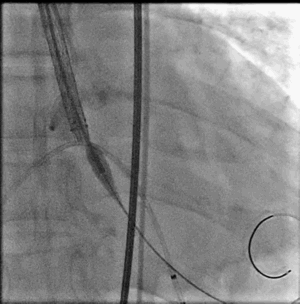

选择BaIt23球囊进行预扩

结合术前CT判断和术中影像判断,最终决定植入L26号venus A瓣膜。采取标准位置释放。

一开始可以将ring释放到mark点往下2mm处,暂停释放张力,造影观察位置,此时仍可以轻松上下调整